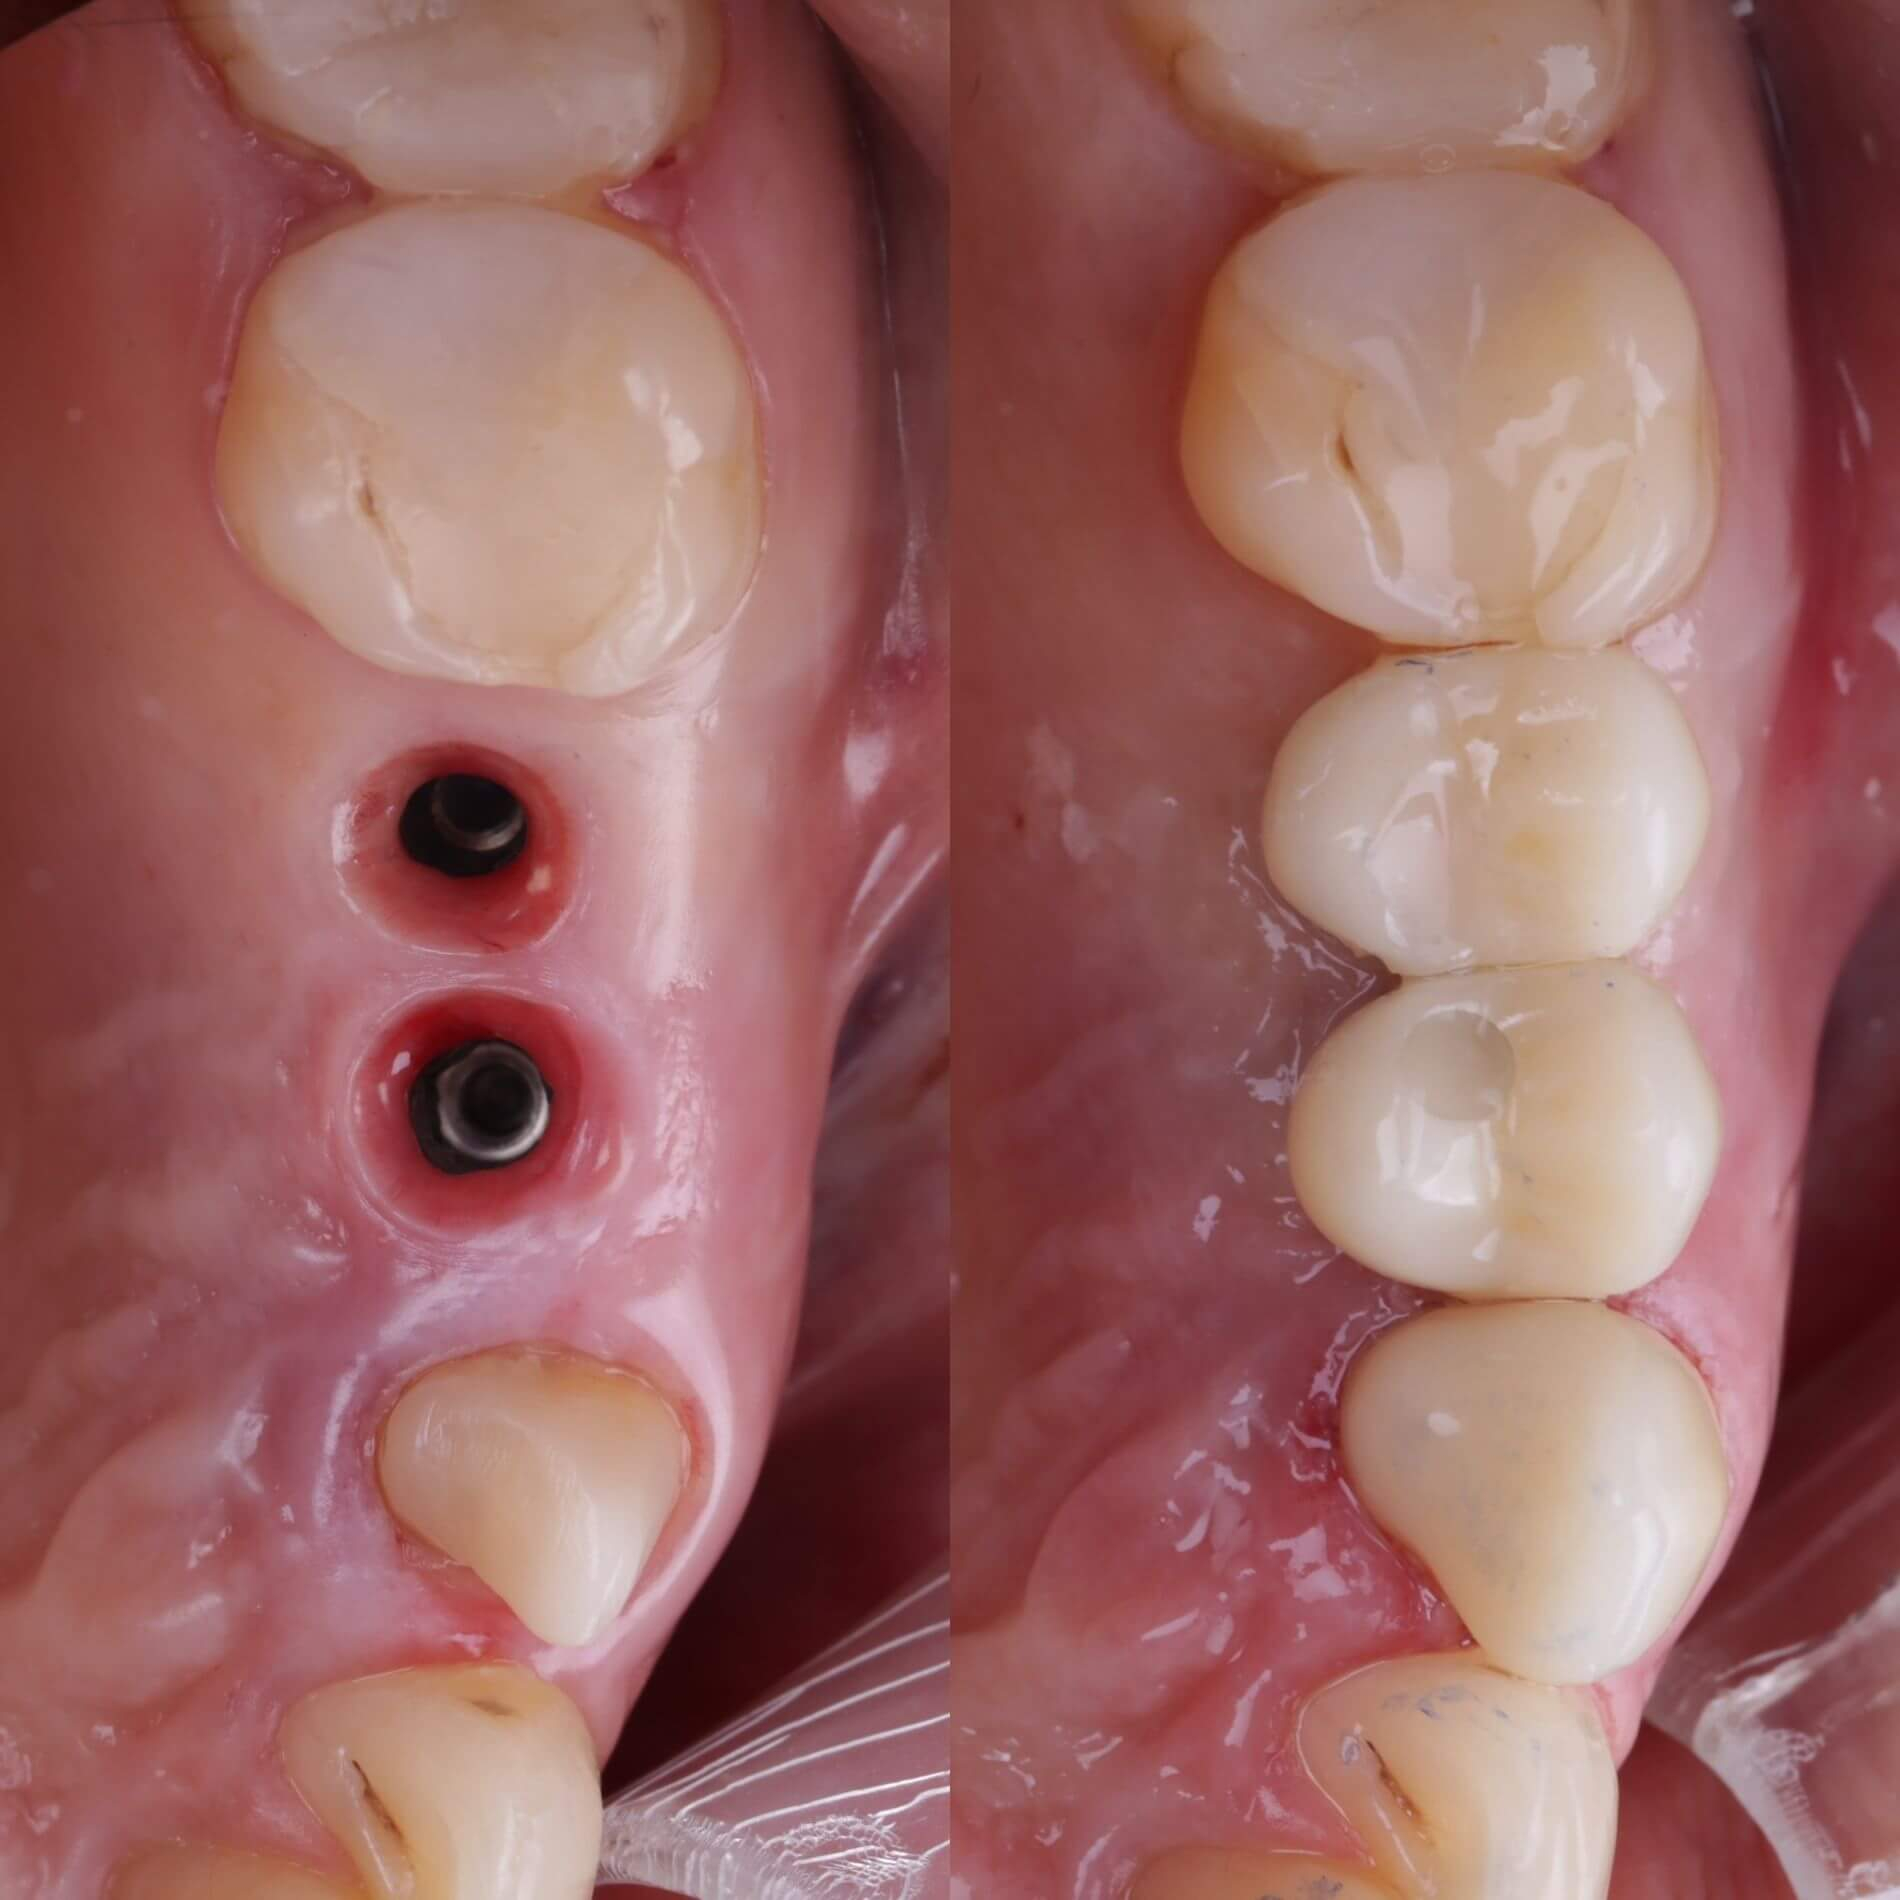

Галерея